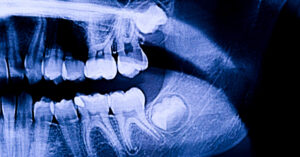

If you’re considering wisdom teeth removal in Lethbridge, it’s normal to have questions about the process. At Lethbridge Dental Services South, we start with a consultation and X-rays to understand how your wisdom teeth are positioned and to discuss whether extraction is recommended. On the day of your procedure, local anesthesia ensures your comfort, and sedation options are available for those who want a calmer experience. The removal is done carefully to protect surrounding teeth and tissues. After the procedure, we provide clear guidance on managing swelling, soreness, and daily care, so you know exactly what to expect during recovery. Our team is always available to answer questions and offer support at every stage, helping you feel prepared and informed.

Impacted wisdom teeth don’t always cause immediate pain, but they can lead to swelling, tenderness, or discomfort at the back of the mouth. Other signs include difficulty opening the mouth fully, jaw stiffness, or pressure on neighboring teeth. Regular dental check-ups and X-rays in Lethbridge can help identify impacted teeth early, allowing your dentist to recommend appropriate care before problems develop.